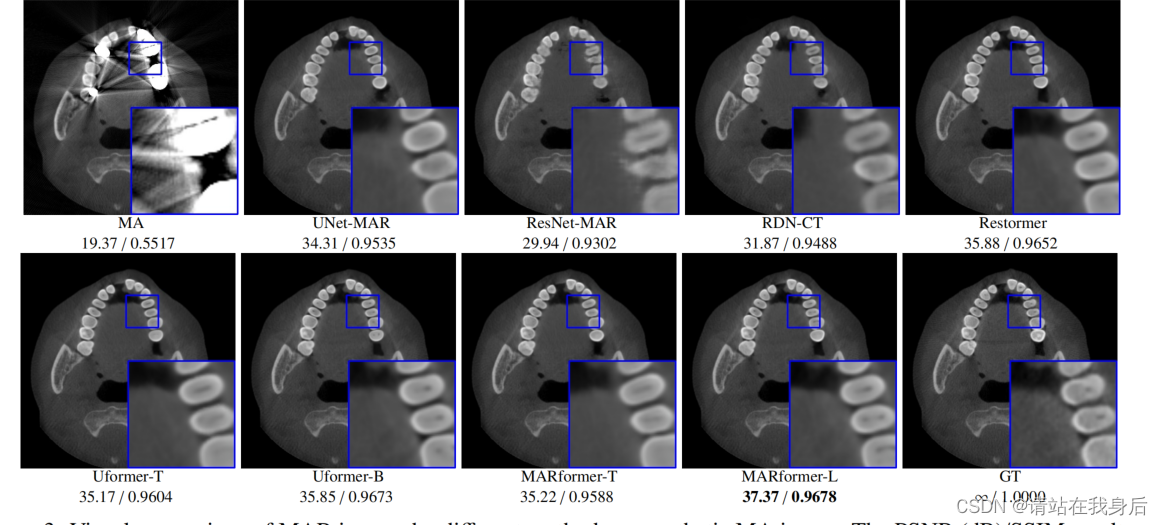

数据就不看了,看两张图

效果可以说好的离谱